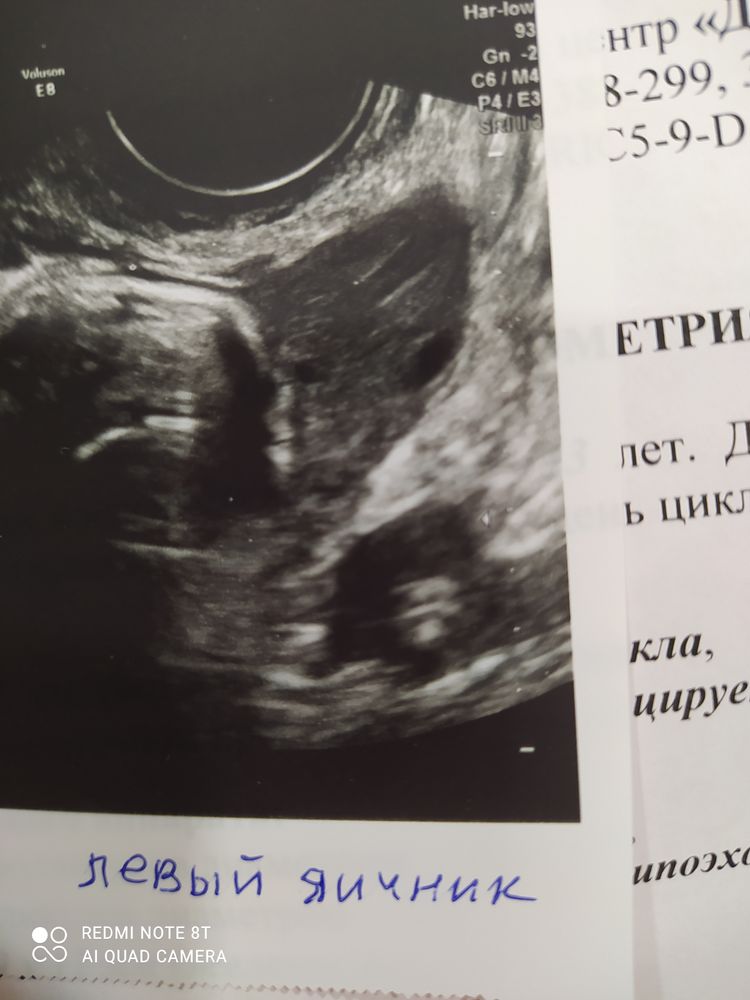

ФолликулометрияДобрый день! Как у вас выглядит по описанию ЖТ по УЗИ? Овуляцию не ощутила никак, пошла на УЗИ на 14 ДЦ, предположительно это оказалось 1 дпо. В яичнике Гипоэхогенное образование с нечёткими контурами 19 на 12 мм. Узист сказал, что скорее всего это ЖТ. Но нет жидкости в пространстве задиматочном. Также сказал, что эта жидкость могла быстро всосаться. Кто разбирается в УЗИ, скажите, это может быть жт?

Эля, както непонятно замерял, никаких линеечк на изображении нет. Сходила в неизвестный ранее мне центр. До этого ходила в клинику и там всё хорошо и понятно замеряли. А тут какая-то непонятность. Я даже на фото не разберу, где яичник и где это оброзование)) но я видела, как узист смотрел кровоток и какую-то пульсацию. Там изображение цветное появлялось на экране. Сказал, что скорее это и есть жт

Есть Дочка-Хочу ещё Сыночка, нда, по такому узи без 100 граммов не разберёшься 😂, желаю вам удачи!!! Скорейшей победы и здоровых//.